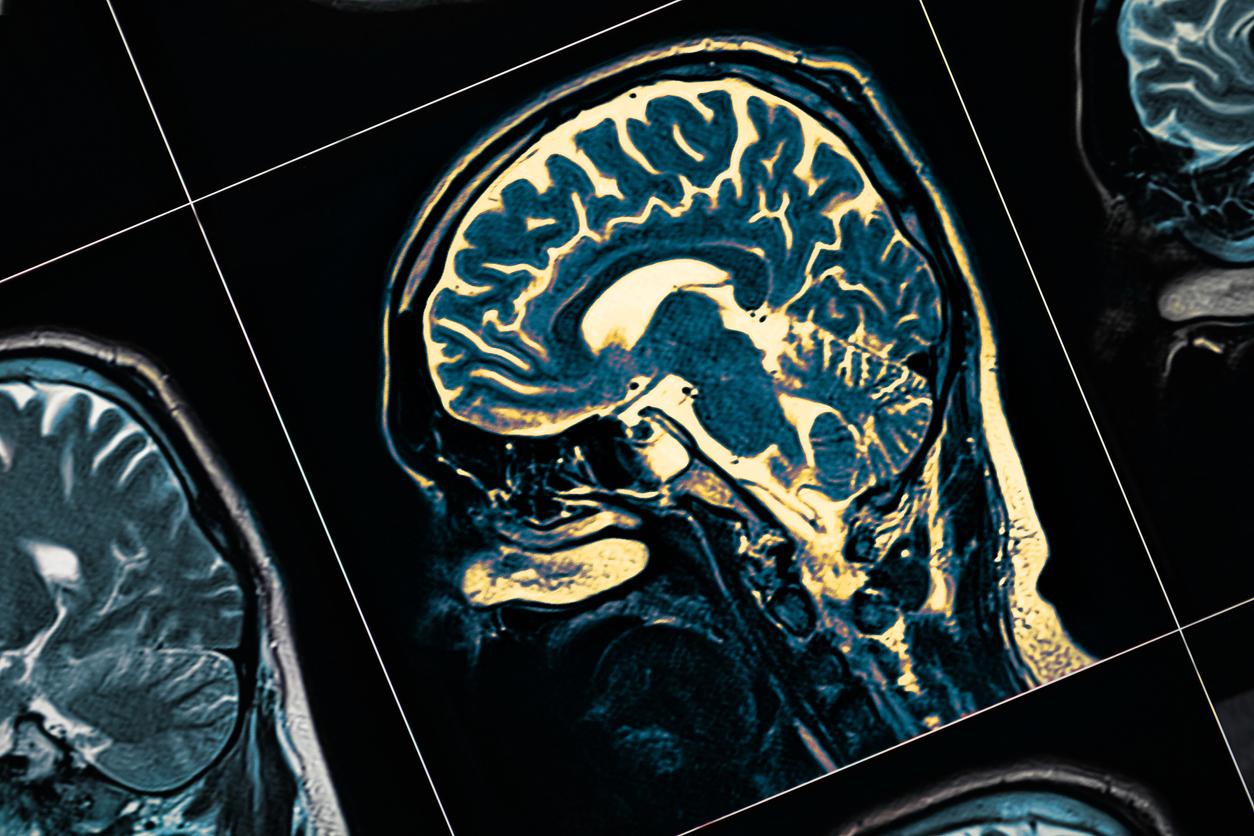

En France, 160 000 personnes sont atteintes de la maladie de Parkinson, selon l’Institut national de la santé et de la recherche médicale (Inserm). Après Alzheimer, il s’agit de la deuxième pathologie dégénérative la plus fréquente dans l’hexagone. Celle-ci se caractérise par trois principaux symptômes moteurs, qui permettent d’établir le diagnostic. Les tremblements tout d’abord, qui concernent surtout les mains et les bras. L’akinésie ensuite, c’est-à-dire lorsque l’individu ressent une lenteur dans la mise en œuvre et la coordination de ses mouvements. Et, enfin, l’hypertonie, qui est une rigidité anormale des muscles.

Le dépistage le plus tôt possible est très important car il permet de débuter la prise en charge au début de la pathologie car, actuellement, aucun traitement ne permet de guérir de Parkinson. Les seules solutions proposées aux malades consistent à améliorer leur qualité de vie et à ralentir la progression de la maladie, notamment l’administration de dopamine qui compense les effets liés à la neurodégénérescence. En effet, au niveau cérébral, Parkinson se caractérise principalement par la dégénérescence progressive des neurones à dopamine. Il s’agit d’un neurotransmetteur très important pour de nombreuses fonctions dont les mouvements.